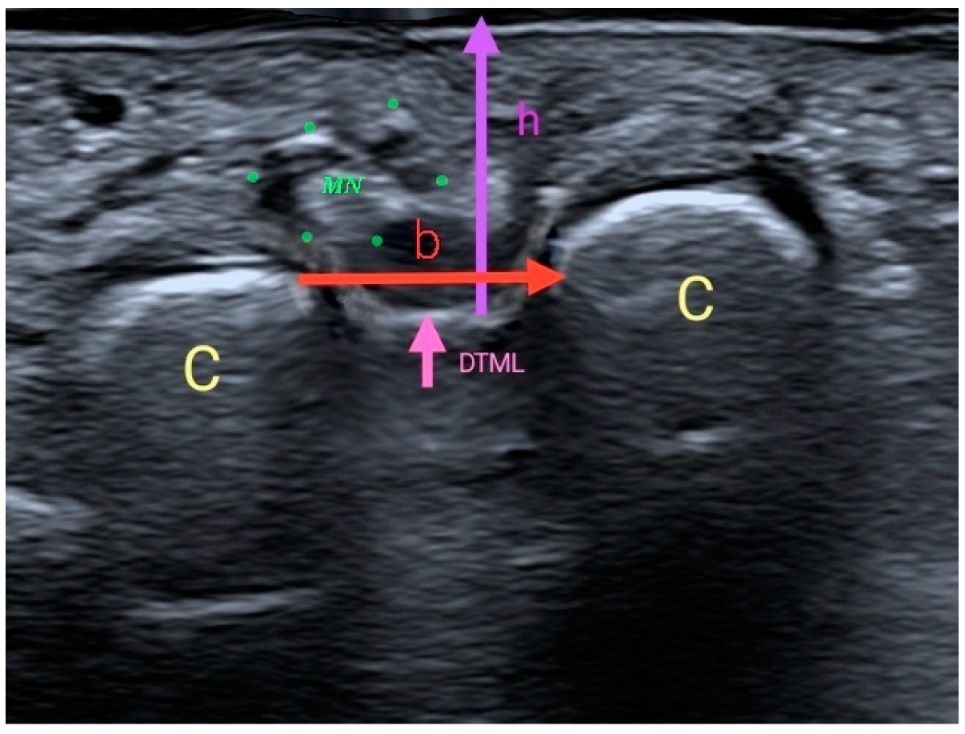

- Ruiz-Herrera, M.D.M.; Marcos-Tejedor, F.; Aldana-Caballero, A.; Calvo-Lobo, C.; Rodriguez-Sanz, D.; Moroni, S.; Konschake, M.; Mohedano-Moriano, A.; Aceituno-Gómez, J.; Criado-Álvarez, J.J. Novel Ultrasound Anatomical Measurement of the Deep Transverse Metatarsal Ligament: An Intra-Rater Reliability and Inter-Rater Concordance Study. J. Clin. Med. 2022, 11, 2553. [Google Scholar] [CrossRef]